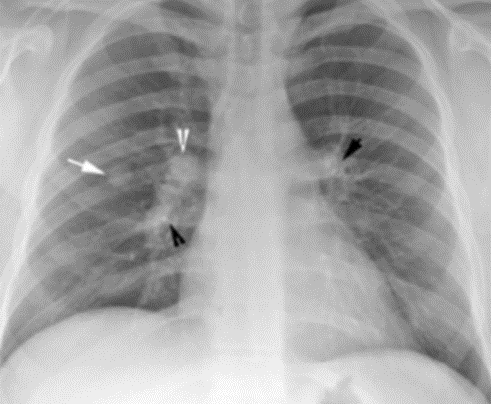

3. 폐결절 발견 방법: 흉부 X-ray, CT 검사

| 요약 | 대개 무증상, 흉부 방사선 촬영과 CT 검사로 발견 |

| 방법 | 흉부 X선 촬영, 흉부 CT 촬영 |

| 특징 | 과거 검사 결과와 비교하여 크기 변화 확인 |

폐결절은 대개 무증상이며, 대부분 흉부 방사선 촬영을 통해 발견됩니다. 최근에는 국가암검진 저선량 CT 검사에서도 폐결절이 발견되기도 합니다. 이는 조기 발견의 중요성을 강조하는 대목입니다.

폐결절의 진단은 주로 흉부 X선 촬영과 흉부 CT 촬영을 통해 이루어집니다. 흉부 X선 검사에서는 과거 검사 결과와 비교하여 결절의 크기 변화를 확인합니다. 이를 통해 결절의 성장 속도와 성격을 파악할 수 있습니다.

정확한 진단을 위해서는 여러 번의 검사가 필요할 수 있으며, 특히 결절의 크기와 모양이 변화하는지를 주의 깊게 관찰해야 합니다.